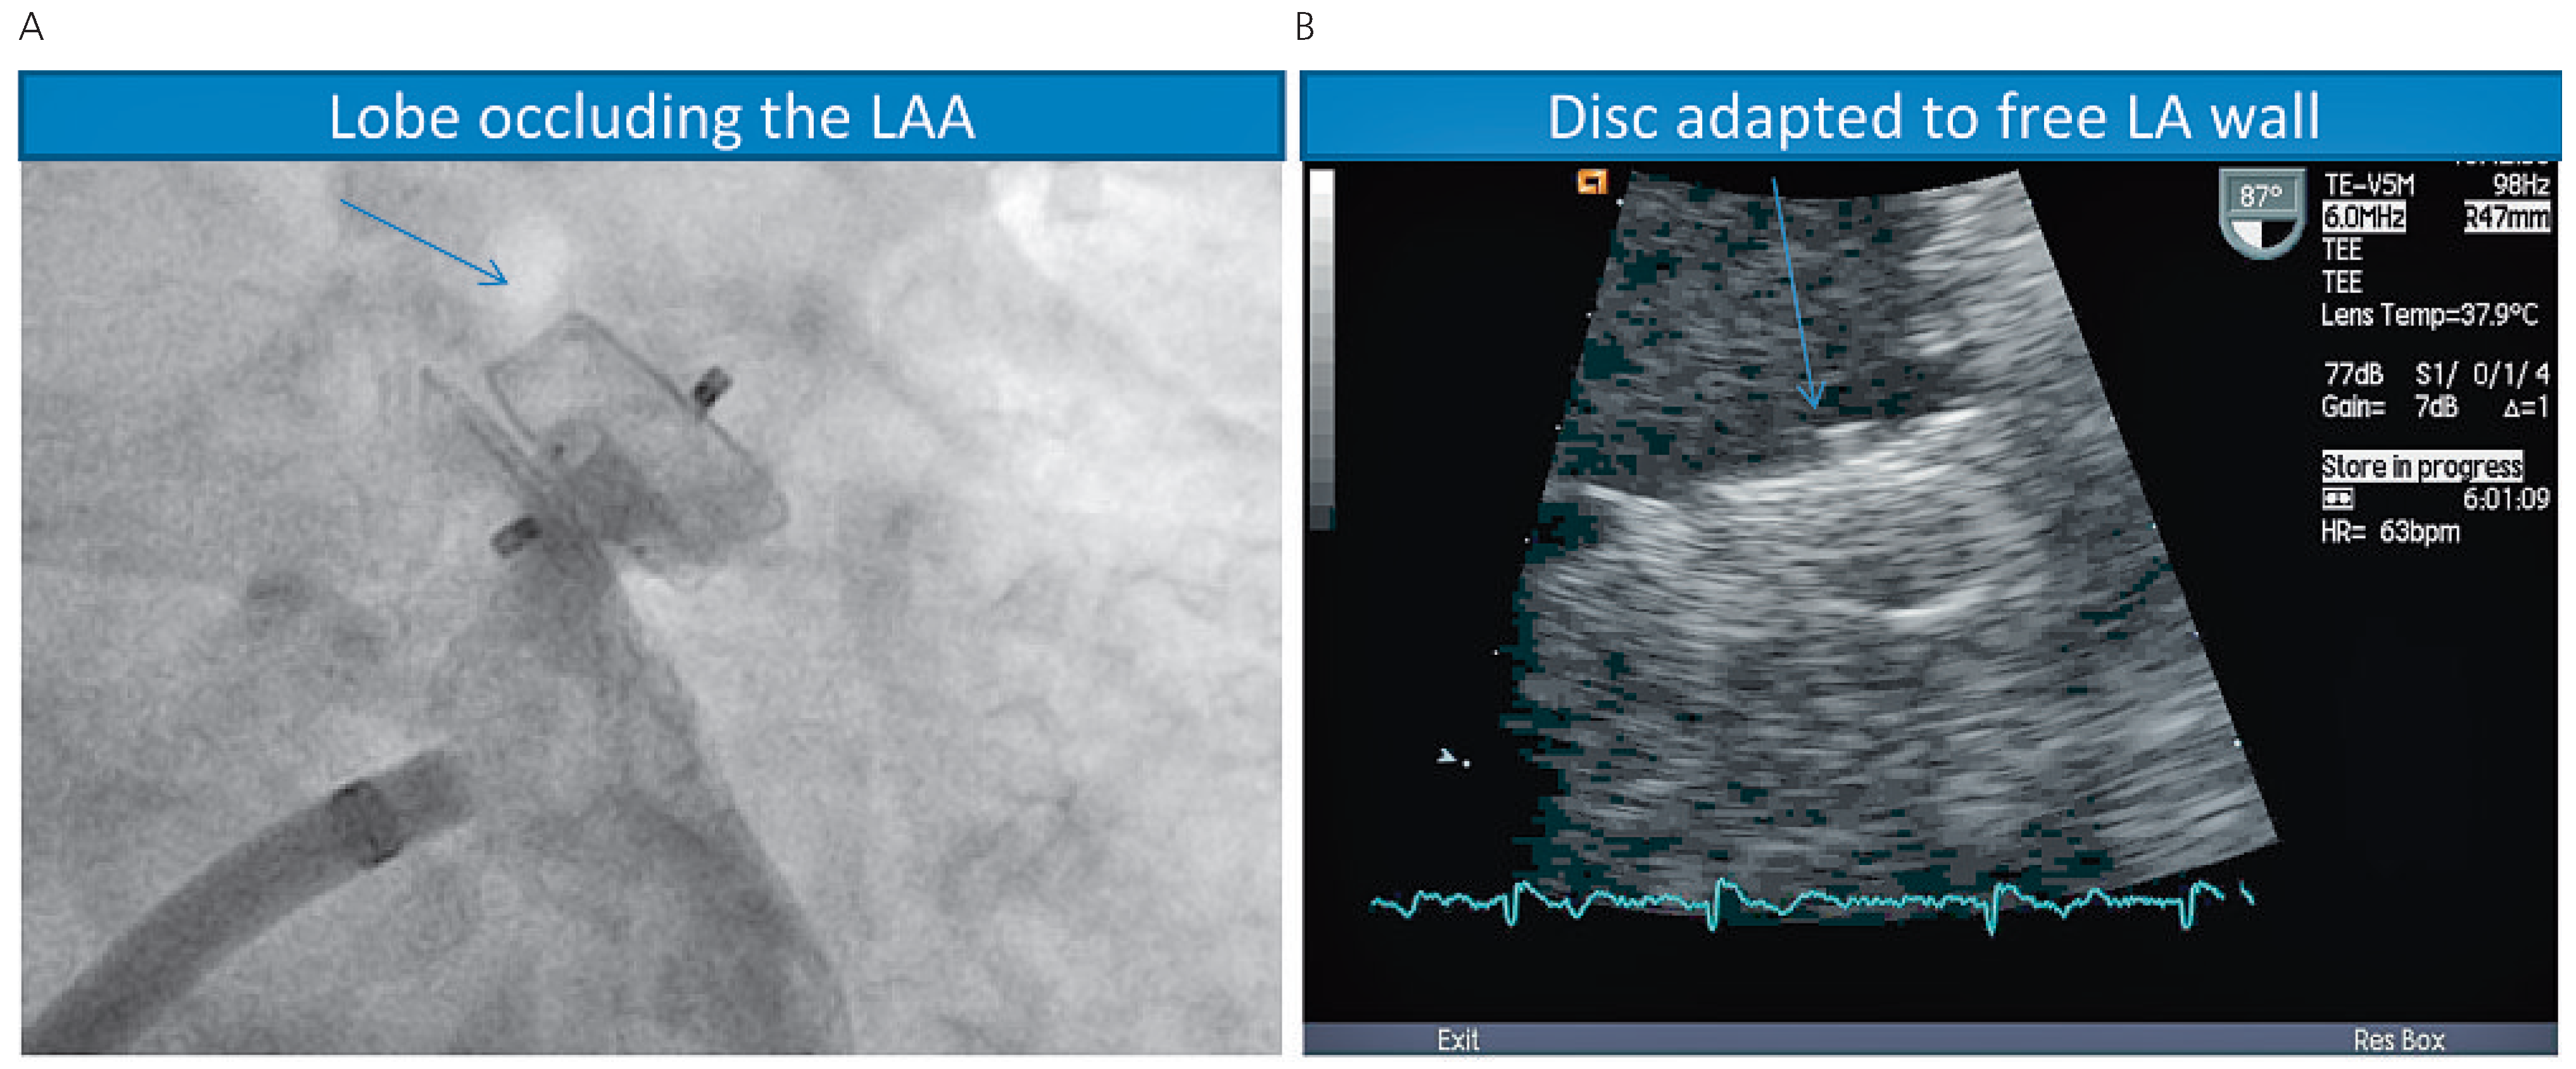

Amplatzer devices